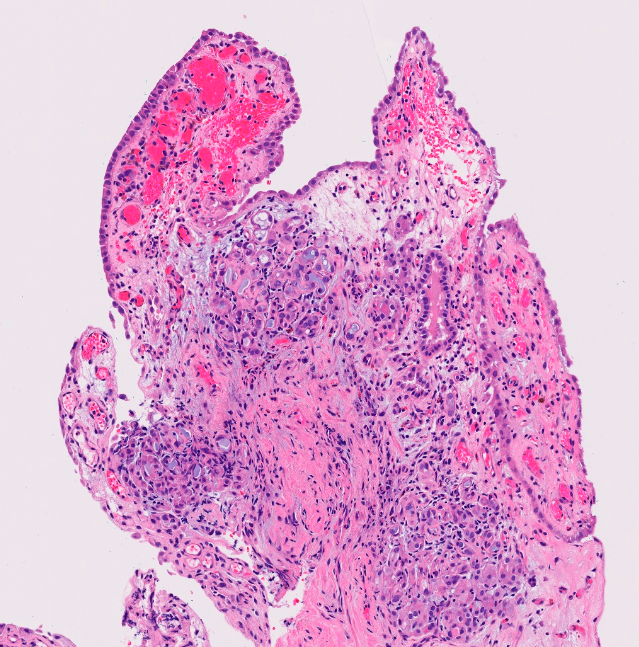

Dx

LS (lymphocytic depletion subtype)

Sclerotic band replacing the lamina propria, globular and perivascular hyalinization and scarce lymphocytic infiltrate is seen. The overlying epithelium shows moderate atypia, corresponding to differentiated penile intraepithelial neoplasia.